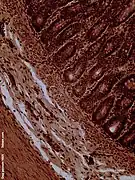

Dog jejunum (magnified 100-fold)

The jejunum contains very few Brunner's glands (found in the duodenum) or Peyer's patches (found in the ileum). However, there are a few jejunal lymph nodes suspended in its mesentery. The jejunum has many large circular folds in its submucosa called plicae circulares that increase the surface area for nutrient absorption. The plicae circulares are best developed in the jejunum.

There is no line of demarcation between the jejunum and the ileum. However, there are subtle histological differences:

- The villi of the jejunum look like long, finger-like projections, and are a histologically identifiable structure.